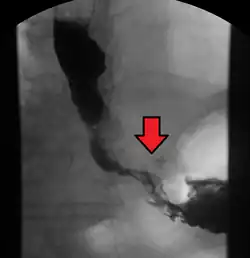

Esophageal cancer as shown by a filling defect during an upper GI series

Although an occlusive tumor may be suspected on a barium swallow or barium meal, the diagnosis is best made with an examination using an endoscope. This involves the passing of a flexible tube with a light and camera down the esophagus and examining the wall, and is called an esophagogastroduodenoscopy. Biopsies taken of suspicious lesions are then examined histologically for signs of malignancy.